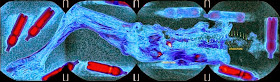

MRI scanning of 'Princess Ukok' mummy [Credit: 'Science First Hand'/Andrey Letyagin]

'During the imaging of mammary glands, we paid attention to their asymmetric structure and the varying asymmetry of the MR signal,' stated Dr Letyagin in his analysis.

'We are dealing with a primary tumour in the right breast and right axillary lymph nodes with metastases.'

'The three first thoracic vertebrae showed a statistically significant decrease in MR signal and distortion of the contours, which may indicate the metastatic cancer process.'

He concluded: 'I am quite sure of the diagnosis - she had cancer.

She was extremely emaciated.

Given her rather high rank in society and the information scientists obtained studying mummies of elite Pazyryks, I do not have any other explanation of her state.

Only cancer could have such an impact.

'Was it the direct cause of the death? Hard to say.

We see the traces of traumas she got not so long before her death, serious traumas - dislocations of joints, fractures of the skull.

These injuries look like she got them falling from a height.'

General MRI scans [Credit: 'Science First Hand', Andrey Letyagin]

But he stressed: 'Only cancer could have such an impact.

It is clearly seen in the tumour in her right breast, visible is the metastatic lesion of the lymph node and spine...She had cancer and it was killing her.'

Dr Andrey Letyagin; scans show right breast tumor and metastatic lymph nodes in the right axilla and metastases in the spine, surrounded by edematous paravertebral fiber (bottom)

[Credit: The Siberian Times/Andrey Letyagin]